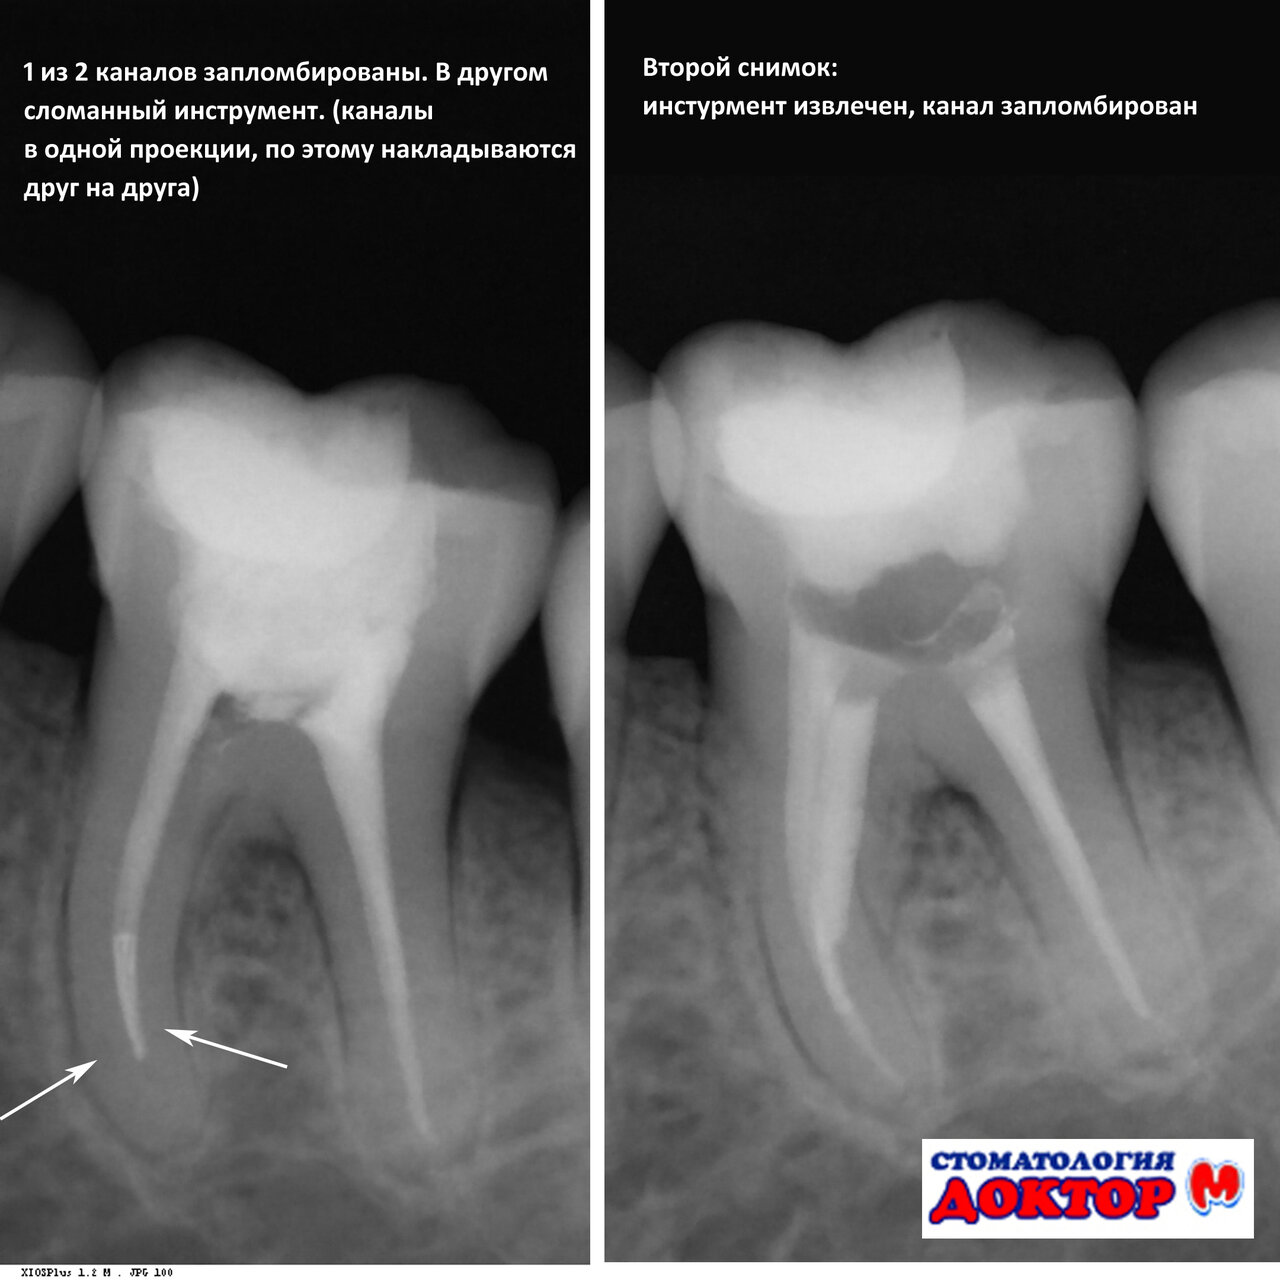

Перелечивала здесь два зуба, шестерки, очень сложные оказались, до этого два доктора сказали что не справятся. У Рустама получилось отлично, каналы вылечены, зубы спасены. А это самое главное. Спасибо, доктор!

- Врачи берутся за сложные случаи, от которых отказались другие.